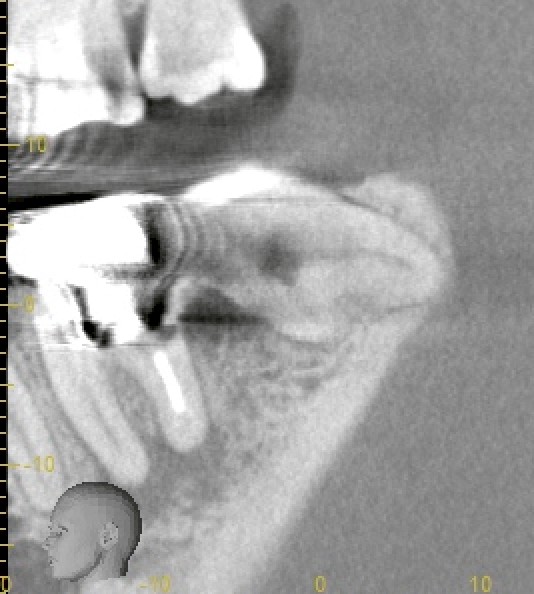

この患者さまの親知らずは二根性で太く、しかも手前の歯が弱っているという難しい特徴がありました。

一時は「移植(歯牙移植)」も検討しましたが、CT精査の結果——

* 抜歯窩とサイズ不一致

* 親知らずの二根が湾曲し、分割抜歯が必要な可能性

* 術後安定性が十分に得られない

これらを踏まえ、移植は適応外と判断。